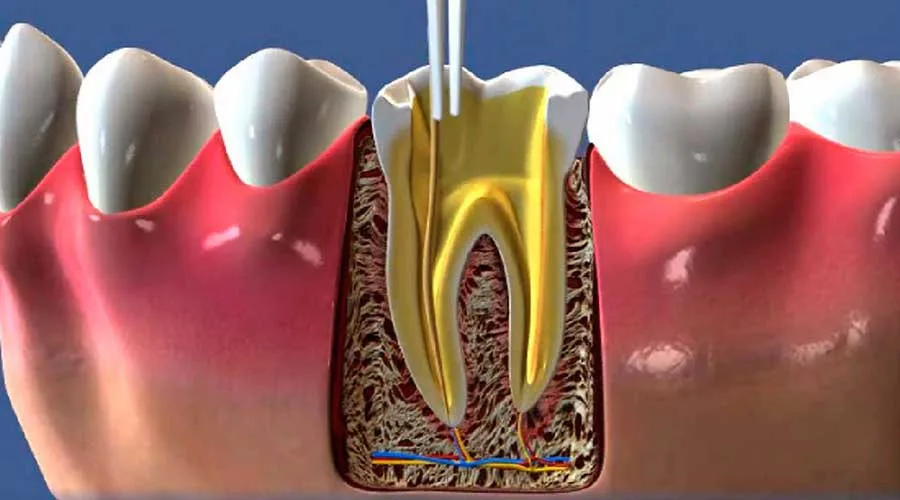

Este procedimento especializado foca em salvar dentes danificados, eliminando a necessidade de extrações e mantendo a integridade da arcada.

Ao remover o tecido infectado, o especialista estabiliza a saúde bucal, fundamentando uma recuperação plena e protegendo o dente contra novas complicações bacterianas.

A inflamação interna causa sensibilidades extremas, e a remoção da polpa comprometida neutraliza essa fonte de sofrimento de forma eficaz:

Manutenção Natural: Preservação do dente original, mantendo a função mastigatória;

Sessão Clínica: Execução do tratamento sob anestesia eficaz, priorizando o bem-estar do paciente;